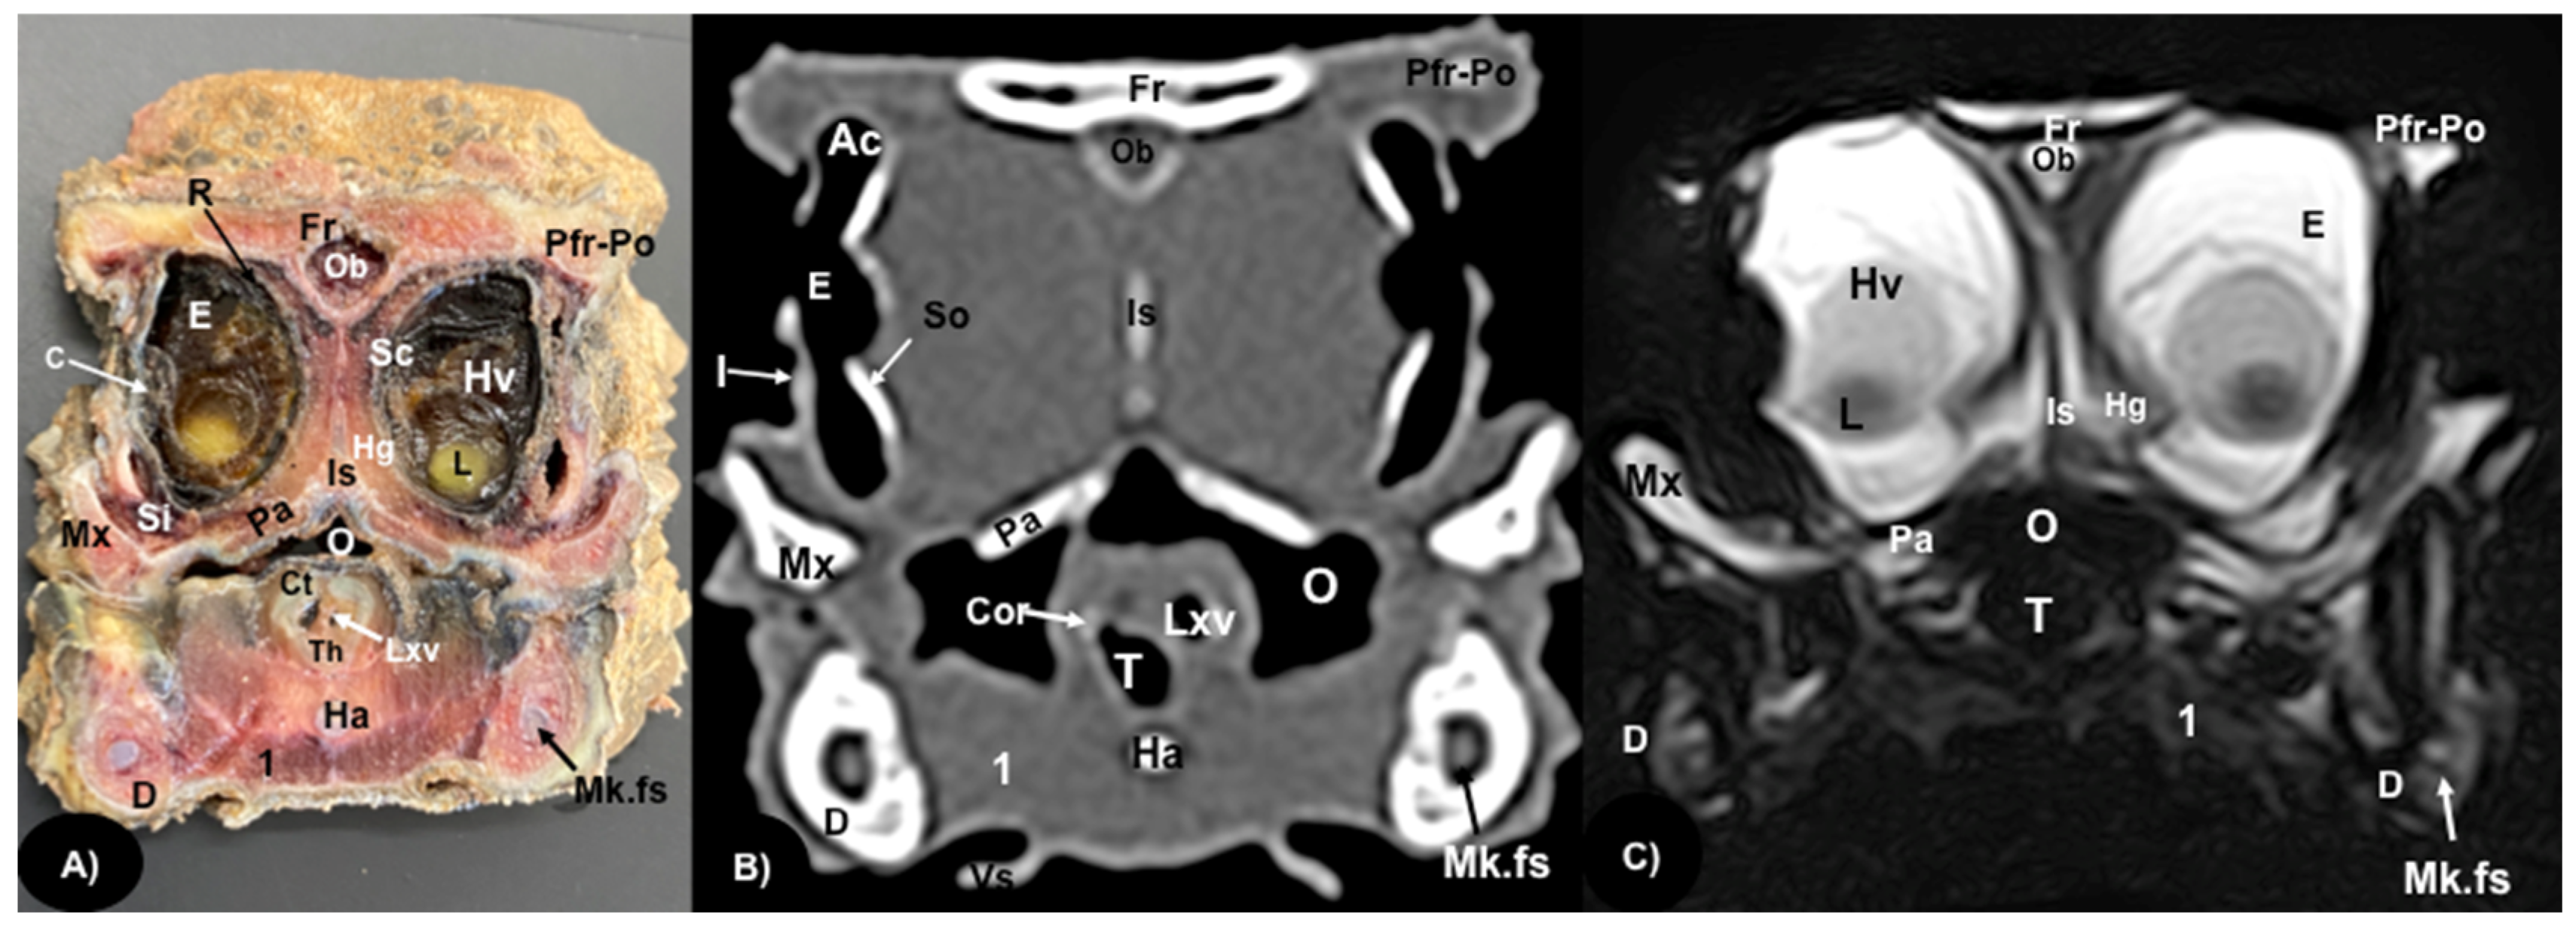

3.1. Anatomical Sections

3.2. Computed Tomography (CT)

3.3. Magnetic Resonance Imaging (MRI)